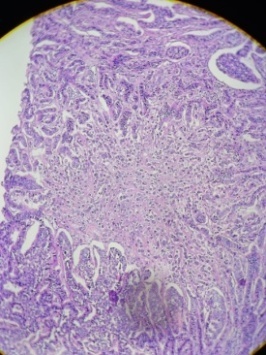

The histopathology section from the right ovary shows a cyst walled by stratified squamous epithelium with skin appendages, hair follicles, mature cartilage, and fat tissue. Thyroid tissue and colloid-filled thyroid follicles made up a portion of the solid nodule (fig. 4)

Fig. 4: Thyroid tissue and colloid-filled thyroid follicles

A tumor cell with sheets of monomorphic cells (fig. 5) with copious amounts of granular cytoplasm organized in nests and an insular pattern was also observed. There is scattered mitosis. The nuclear chromatin had a "salt and pepper" look and was finely granular.

Fig. 5: Sheets of monomorphic cells organized in nests and an insular pattern